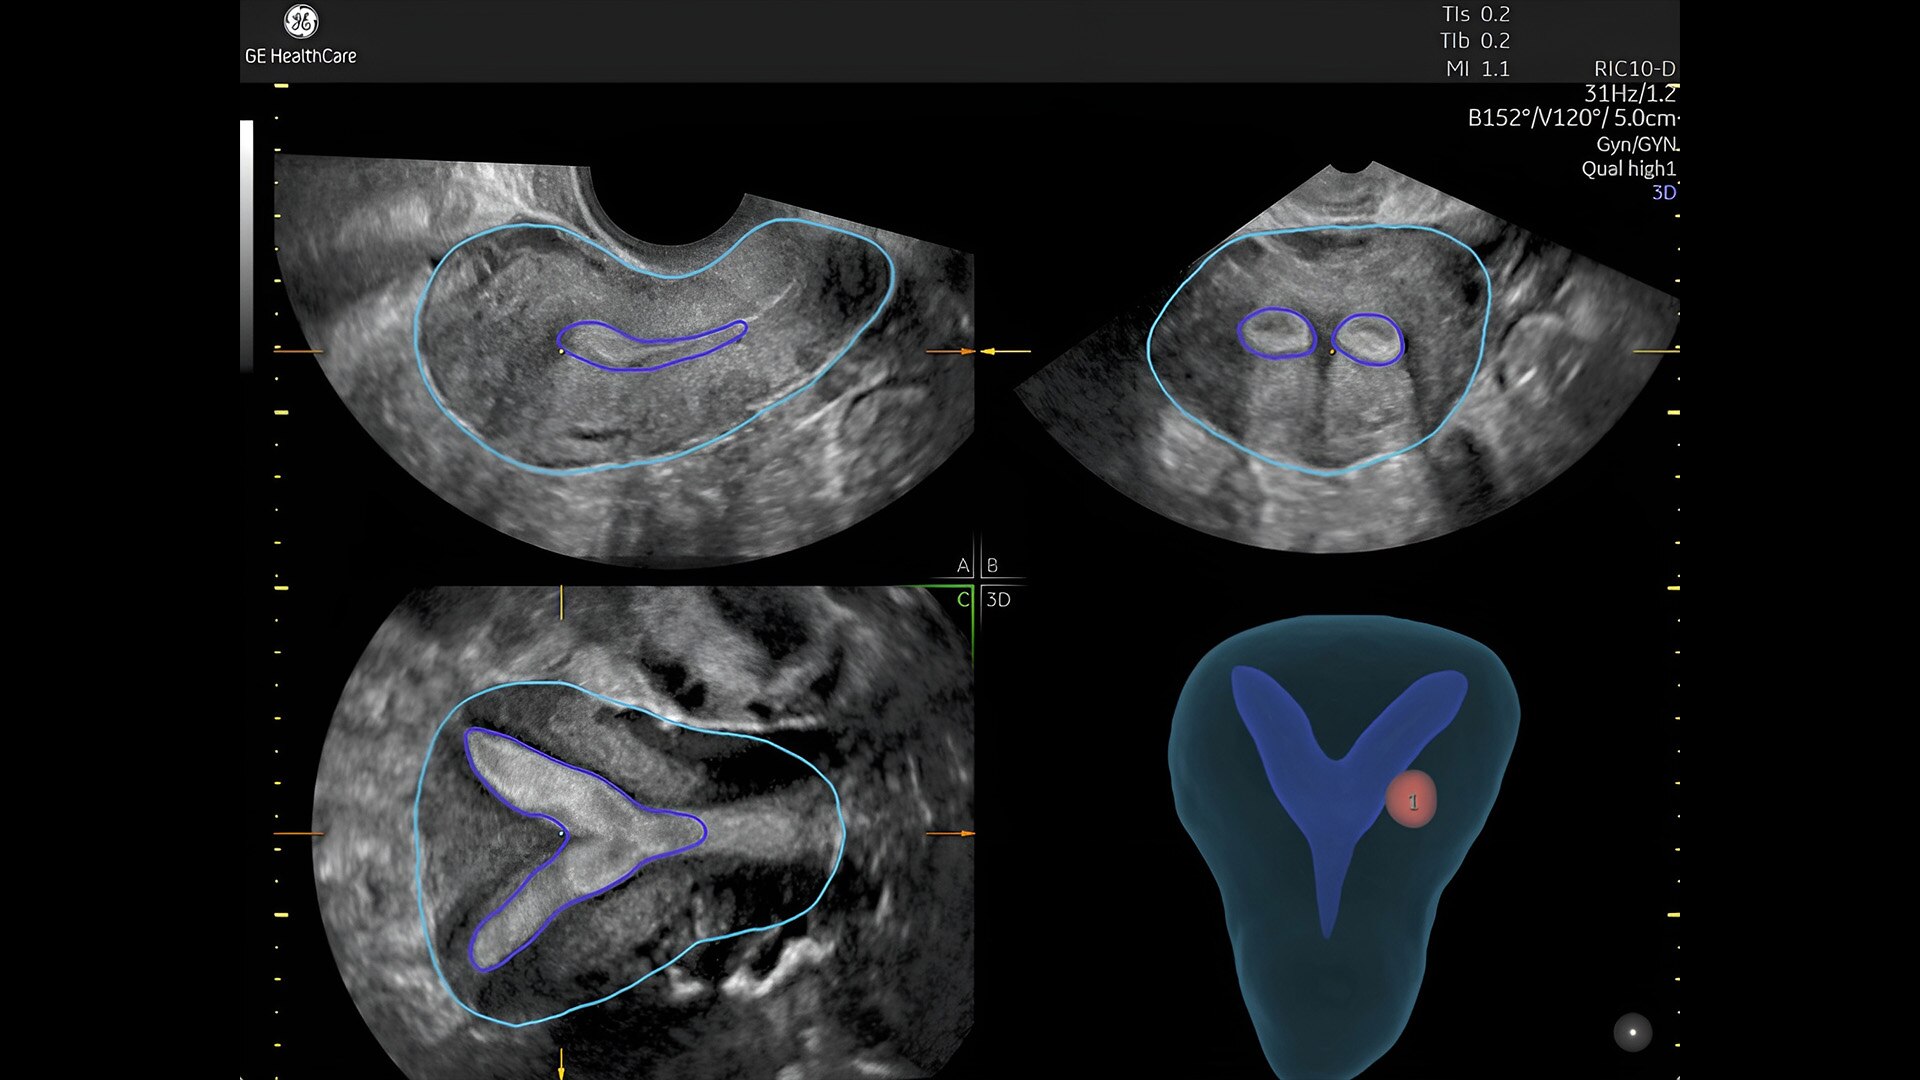

Pelvic health

Offer patient answers faster with Ai-based automation tools

Complex cases come with enough uncertainty. That's why the Voluson Expert 22 is specifically designed for in-depth assessment of complicated anatomy — with pioneering first trimester, fetal cardiac, gynecological, and other pivotal technologies that focus on early detection and intervention.

Detect the undetectable

Discover complicated anomalies and pathologies with the Voluson Expert 22 to provide answers sooner for better decision making.